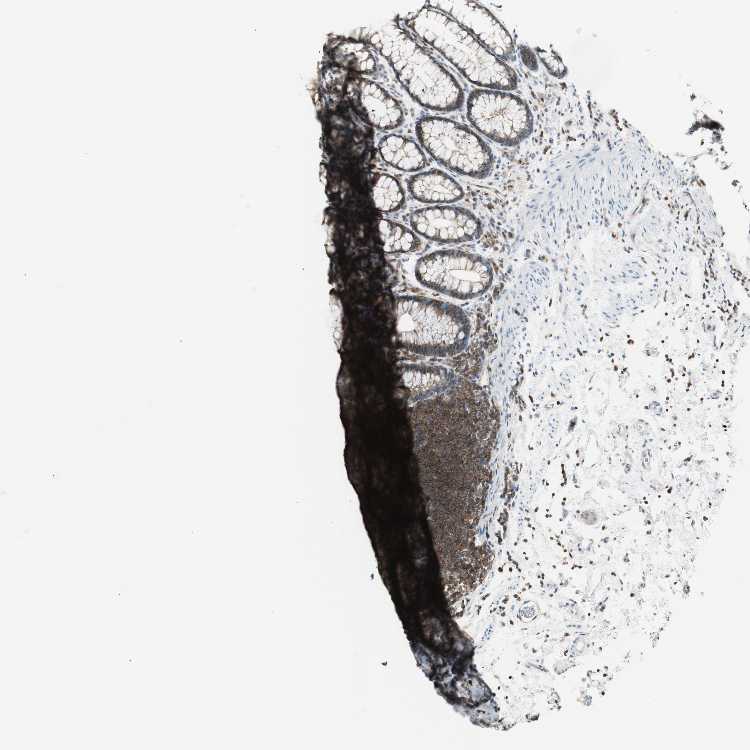

TISSUE PRIMARY DATA RECTUM Show tissue menu

Rectum

RECTUM - Antibody stainingi

Antibody staining in the annotated cell types in the current human tissue is reported as not detected, low, medium, or high, based on conventional immunohistochemistry profiling in selected tissues. This score is based on the combination of the staining intensity and fraction of stained cells.

Each image is clickable and will lead to virtual microscopy that enables deeper exploration of all samples and also displays staining intensity scores, fraction scores and subcellular localization as well as patient and tissue information for each sample.

Antibody HPA046833Antibody CAB004545

Glandular cells HighMedium